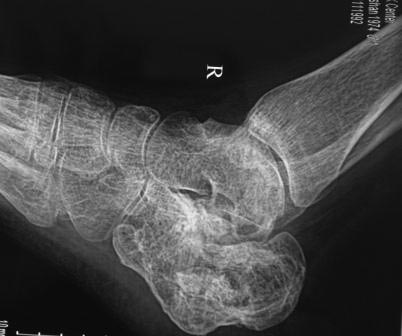

Постравматическая деформация пяточной кости

Уважаемые коллеги. Вчера госпитализирован пациент 1970г.р. , в ноябре 2014г, получил о/перелом пяточной кости. в другой клинике произведена КДО аппаратом Илизарова,

после трех месяцев аппарат сняли? , и больной начал наступать и ходить?- все это со слов б-ного(р-снимков нет.), Жалобы боли при ходьбе к-рая в динамике усиливается, об-но: деформация пяточной кости, движение в г/стоп.суставе почти в польном обьеме, по мед.поверхности пятки рубец плотно спаянный с костью.

Предварительный план: корригируюшая остеотомия пяточной кости, для создания свода стопы.( сможем ли опустить бугра пяточной кости из-за натяжения ахиллово сухожилия), и подтаранный артродез.